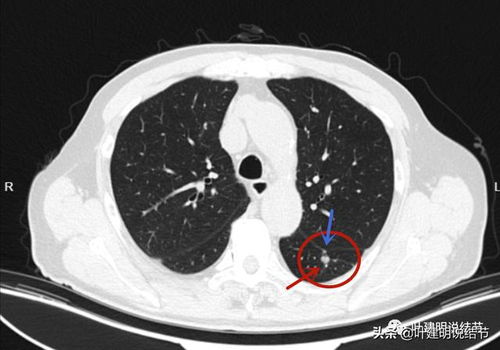

术后复发患者尤其需要警惕,若再次出现腹痛、腹胀等初始症状,应考虑是否有转移的可能。为了准确诊断,建议进行腹部CT、MRI或腹腔镜检查。